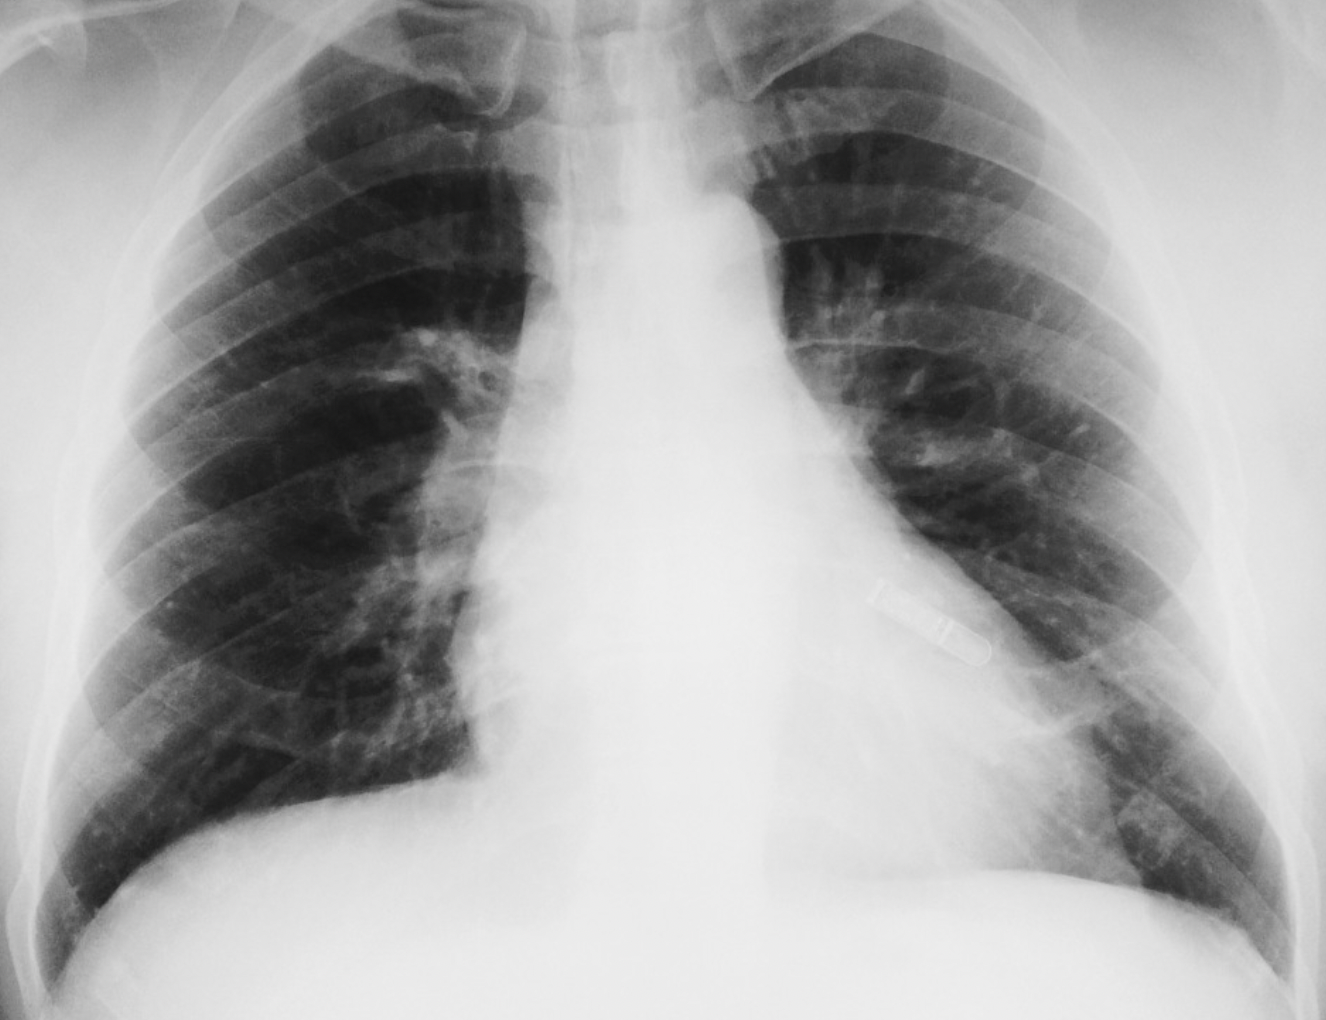

Scimitar syndrome (Anomalous right lower pulmonary vein draining into IVC)